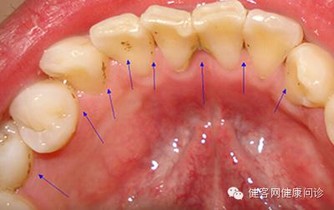

三、刷牙留意牙齒口氣

1、刷牙時如果牙齦出血,很可能是牙周病,因為如果牙齒健康是不會出血的。

牙齒出血也可能與肝病有關。

這種現象在慢性肝病患者中很普遍,還會伴有鼻子流血、月經過多。

主要原因是肝細胞損傷后,肝臟產生凝血因子的功能下降,繼而凝血機制發生障礙。

一般牙出血的肝炎病人可以服用維生素C、維生素K及其他止血藥來緩解病情。